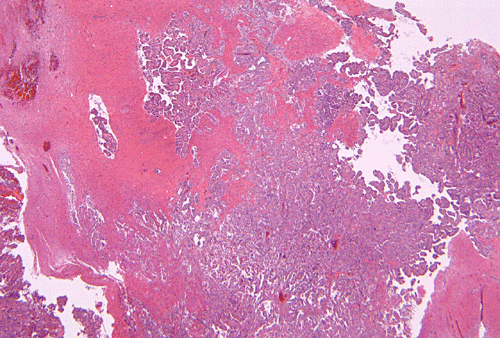

Permanent sections show a papillary epithelial neoplasm with invasion into the brain parenchyma (Panel G, H, and I ). In all areas the tumor cells maintained a single layered architecture. While a papillary structure is present in some area, the tumor cells arrange in a back-to-back cystic architecture intervened by a thin layer of fibrovascular stroma (Panel J). The nuclei are rather bland and monotonous. Mitotic figures are not readily seen  (Panel K). On immunohistochemistry, practically all tumor cells strongly express S100 protein (Panel L) and vimentin (Panel M). Most tumor cells are positive for cytokeratin (AE1/AE3) (Panel N). GFAP is expressed by some tumor cells (Panel O). The Ki-67 labeling index is about 1-2% (Panel P).

Although brain invasion as illustrated in this case is an uncommon event, it has been well documented 5. As per one study on CPPs with brain parenchymal invasion in children, these tumors do not appear to behave in a more aggressive fashion then the non-invasive CPPs 5.